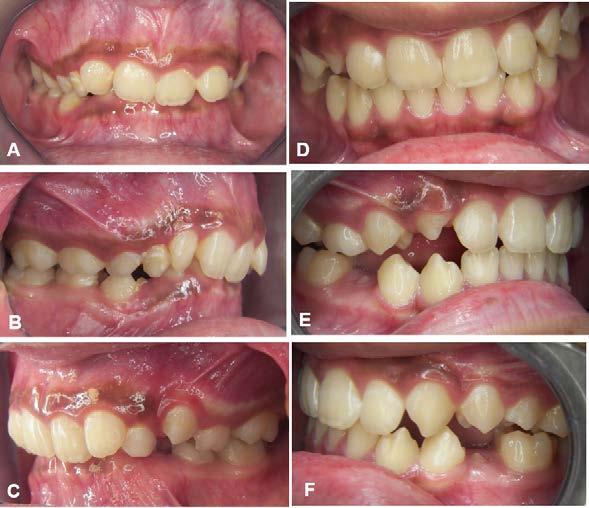

Figura 1. Fotografías intraorales y lateral de cráneo. A. Vista lateral (VL) derecha en oclusión. B. Vista frontal (VF) en oclusión. C. VL izquierda en oclusión. D. Radiografía lateral de cráneo.

Reporte de caso clínico

Paciente masculino de 10 años, se presenta a la consulta en la clínica Gnathos, la mamá reporta desagrado en la estética dental y facial del paciente. En la exploración clínica se observa mordida profunda, amplio número de piezas dentales con caries, fracturas dentales, mala higiene y encías inflamadas. presenta clase II división 2, se le indicaron estudios complementarios para diagnóstico asertivo, modelos de estudio,

Tratamiento de mordida profunda

radiografía panorámica y lateral de cráneo, fotografía intraoral y extraoral, historia clínica y consentimiento informado.

Figura 3. Primer aparto SN1 con almohadillas vestibulares. A. VF con aparato, B. VL derecha C. VL izquierda. D. SN1, vista oclusal (VO). Después de 7 meses del tratamiento se observa los avances obtenidos por el aparato y los ajustes del mismo los cuales observamos en las figuras: E. VO del SN1 7mm de crecimiento transversal, F. VF con aparato, 3G. VL derecha, H. VL izquierda.

Investigación clínica

Figura 4. Segundo Aparato SN1. A. VF con aparato, B. VL derecha, C. VL izquierda, 3D. SN1, VO. Después de 5 meses del tratamiento se observa los avances obtenidos por el aparato y los ajustes del mismo los cuales observamos en la imagen, E. VO del SN1 5 mm de crecimiento transversal, F. VF con aparato, G. VL derecha, H. VL izquierda.

Figura 5. Tercer aparato PIPS A. VF con aparato, B. VL derecha, C. VL izquierda, D. PIPS VO. Después de 7 meses del tratamiento se observa los avances obtenidos por el aparato y los ajustes del mismo los cuales observamos en la imagen, E. VO del PIPS sin los mantenedores de espacio, 5. VF con aparato, 5G. VL derecha, 5H. VL izquierda.

radiculares de O.D. 73 y 83 y rehabilitación oral completa de O.D. 54, 63,65 y 75. Se procedió a colocar aparatos ortopédicos para corrección de la maloclusión en enero del 2022.

El tratamiento inicio con AOF, SN1 con Equiplan adicionando almohadillas vestibulares en el maxilar para despresurizar la acción de la musculatura labial. La indicación de uso fue utilizarlo de forma continua solo retirándose para comer e higienizar, activar del tornillo tanto superior como inferior una vez a la semana, y se realizaron revisiones mensuales en la clínica para valorar avances, llevar

a cabo activaciones, ajustes del aparato e indicaciones. Como se observa en la Figura 3.

Al haber obtenido los avances programados en la corrección de la sobremordida vertical con esté AOF, se decide cambiar a un nuevo SN1, con equiplan sin almohadillas y con arco vestibular esto para continuar regularizando el plano de oclusión en el paciente, y fue utilizado por 5 meses de forma continua. Se mantuvieron las mismas indicaciones de uso, que en el aparato anterior. Como podemos observar en la Figura 4

El AOF Sn1 logró el avance mandibular, expansión programada, armonización de arcadas y regularización de la curva de Spee, entonces se determina cambiar dicho aparato por unas PIPS, clase I para mantener el espacio que corresponde a los O.D. 35 y 45, ya que fueron indicadas para extracción los O.D. 75 y 85, esperando la erupción de premolares para terminar el anclaje. Las indicaciones para el paciente fueron uso continuo de las PIPS por 3 meses, solo retirándose para comer e higienizar, revisiones mensuales en la clínica para activación y desgastes de los mantenedores de espacio, vigilando la erupción de los premolares. Posteriormente se indicó su uso nocturno por 4 meses más para mantener estabilidad de los resultados obtenidos.

Después de 18 meses de tratamiento con ortopedia funcional de los maxilares, podemos hacer una comparativa de los resultados obtenidos.

Figura 6. Fotos intraorales antes y después del tratamiento. A. VF B. VL derecha, C. VL izquierda, después de 18 meses de tratamiento D. VF, E. VL derecha, F. VL izquierda.